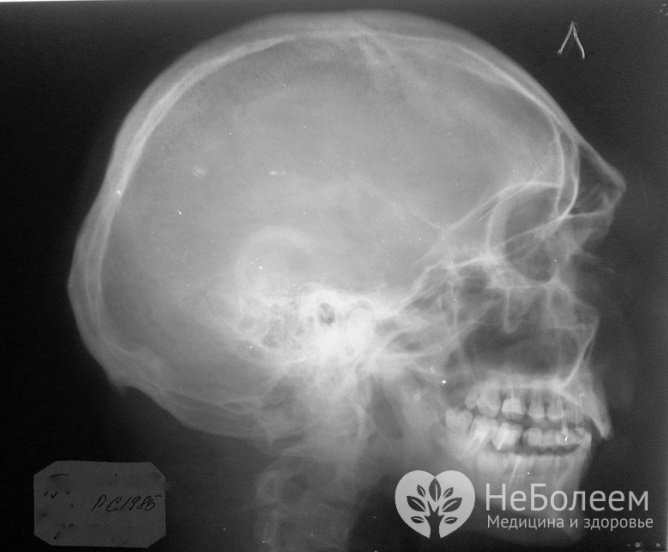

Для уточнення діагнозу може знадобитися проведення рентгенографіїПри проведенні оцінки загального стану необхідно визначити неврологічний статус і обсяг крововтрати. Для виключення перелому або визначення його локалізації проводиться рентгенографія кісток органу в бічній і, можливо, прямій проекції.

У дітей молодшого віку трактування даних рентгенологічного дослідження утруднена, оскільки лицьові кістки у них тонкі, обызвествлены не до кінця і дають слабовыраженную рентгеноконтрастную тінь, на яку відбувається нашарування інтенсивної тіні зубних зачатків і зубів.

При закритій травмі діагностика ускладнюється набряком тканин. При необхідності уточнення діагнозу може знадобитися проведення КТ (комп’ютерної томографії) кісток та придаткових пазух носа.